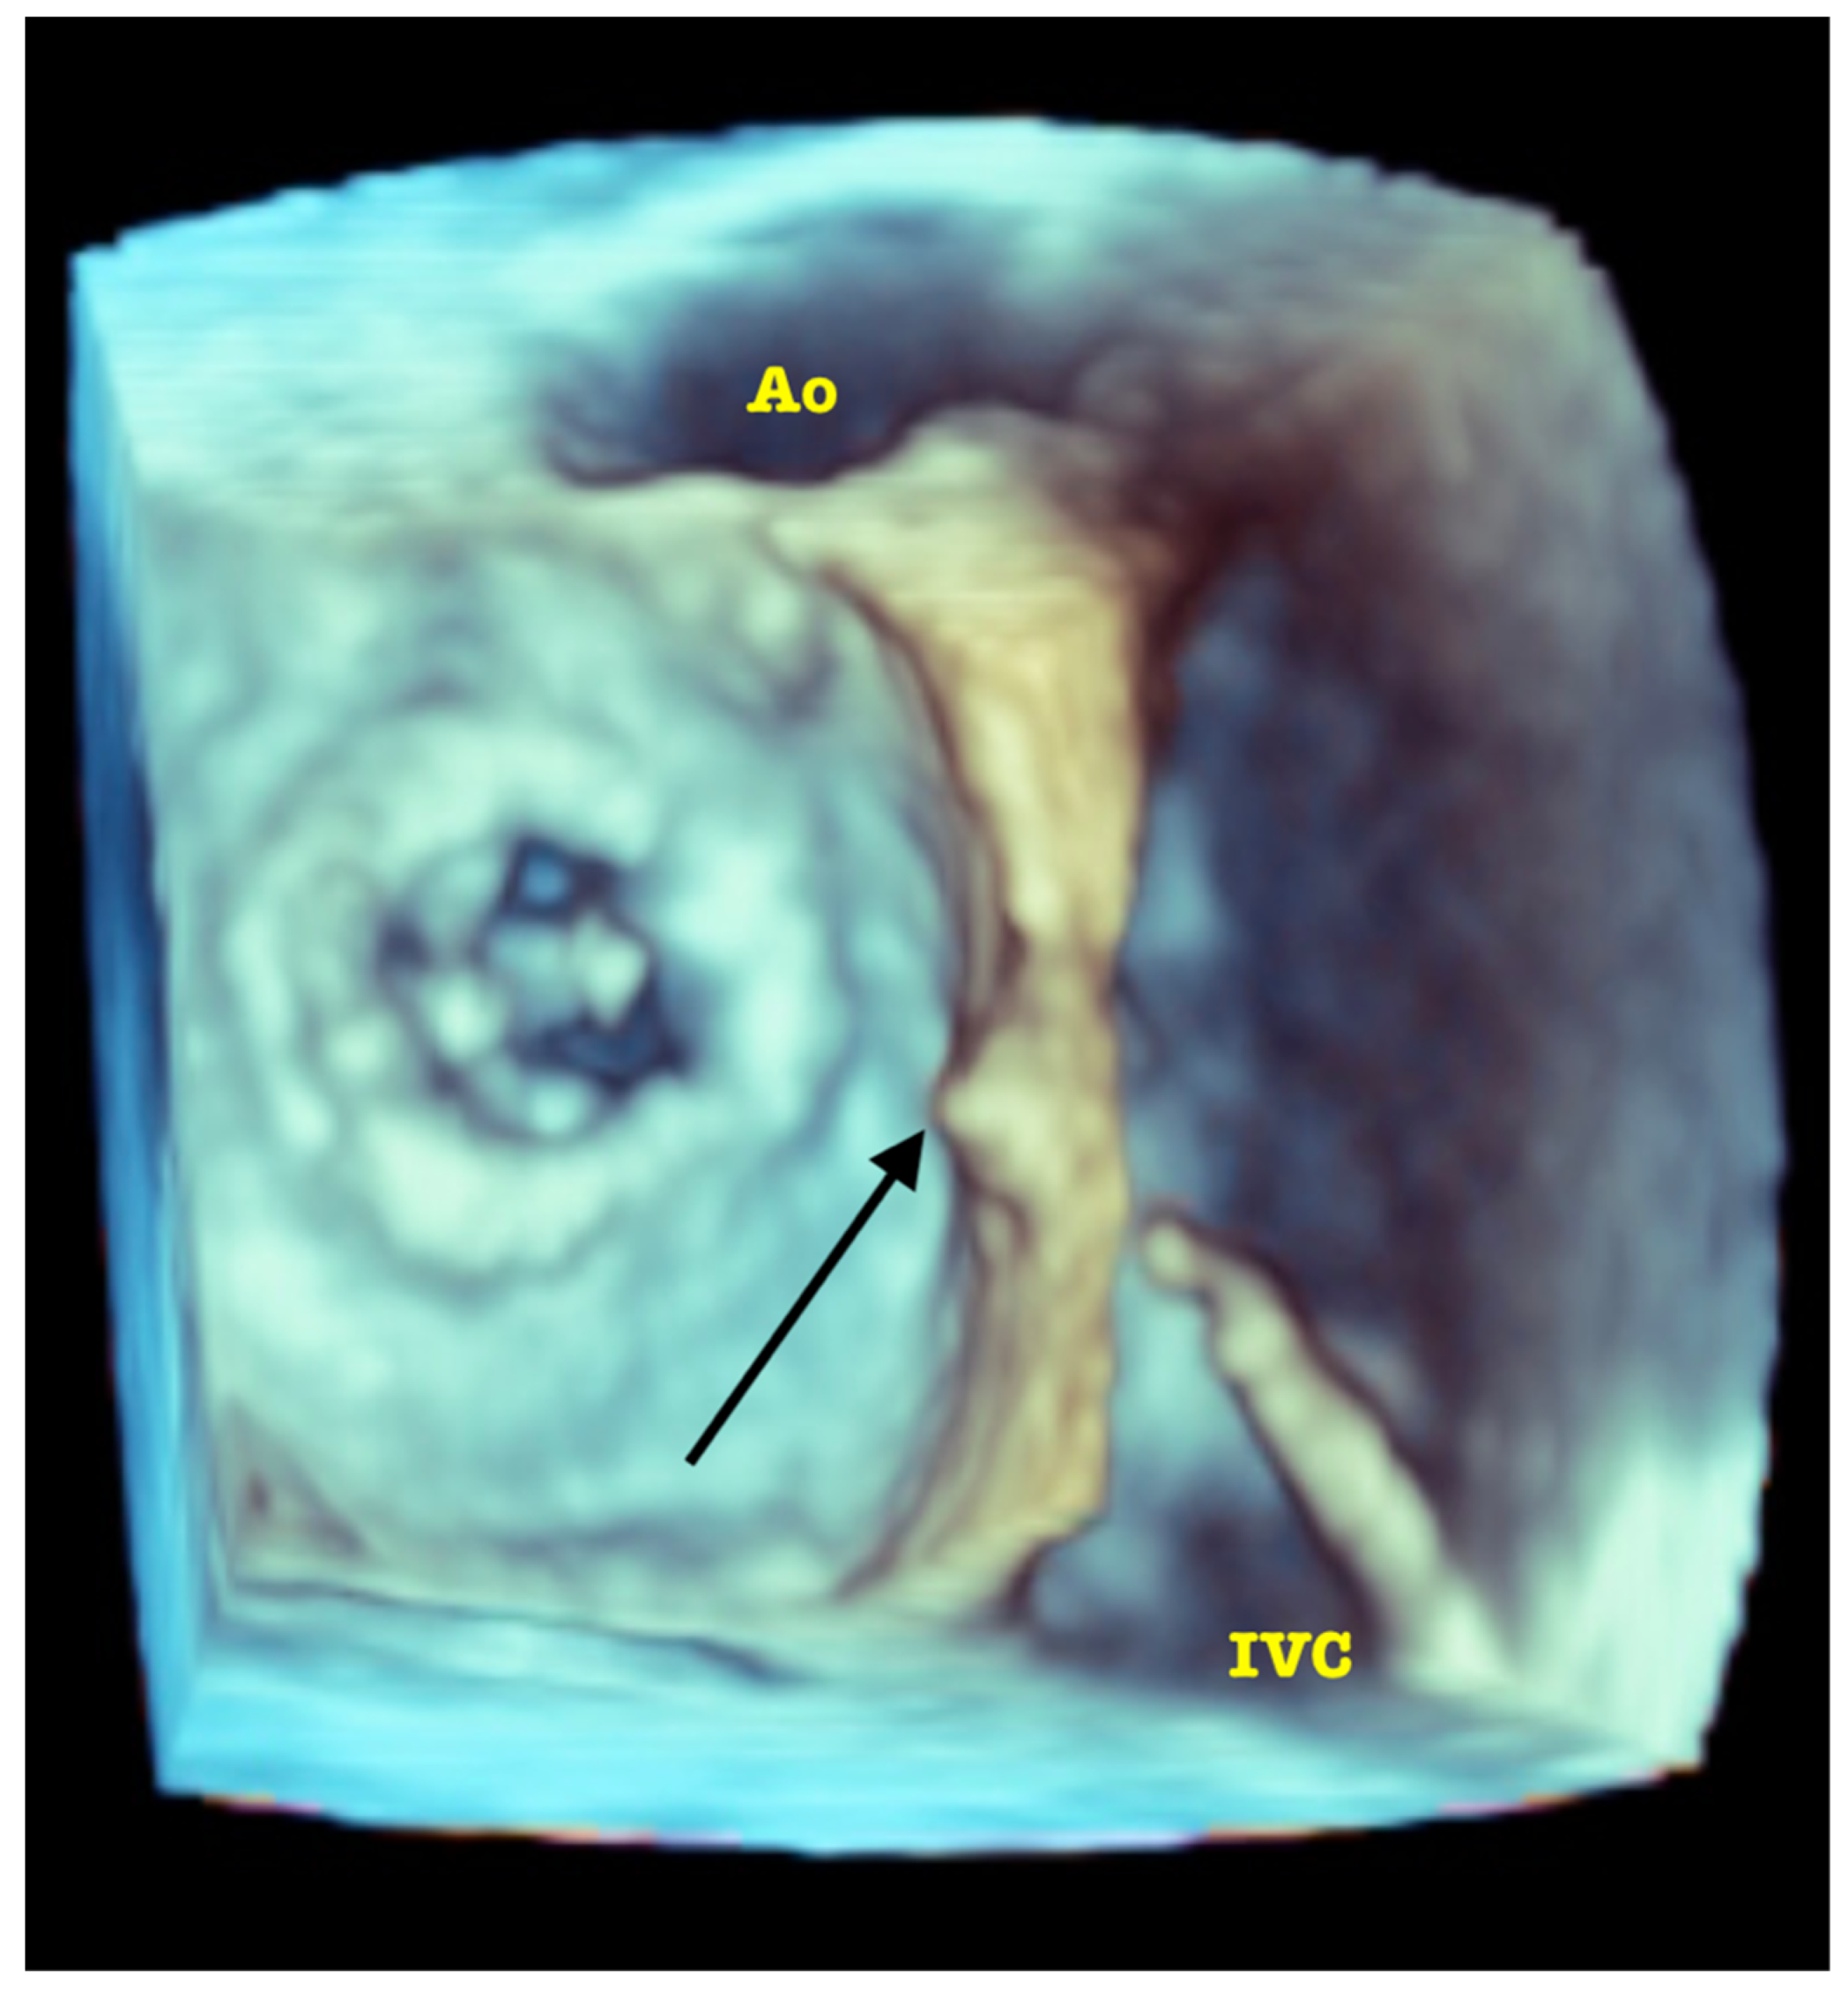

Based on this analysis, a choice can be made between the two devices currently registered for transcatheter PVL closure in the EU and the USA. For regular (oval/round) and short channels (<5 mm) with no structures (e.g., calcifications) preventing apposition of discs, a paravalvular leak device (PLD, Occlutech) is selected. For the irregular ones with long channel (>5 mm), calcifications and/or prosthesis horns in the vicinity of PVL Amplatzer Valvular Plugs 3 (AVP3, Abbott) implanted in a multiplug technique appear to be a better option. In both scenarios, high safety and efficacy have been reported [8,9]. Fairly recently, new 3D image rendering techniques have been introduced to allow, first, the visualization of the morphology of the PVL channel in an even more detailed way, and later, to efficiently guide the procedure [10]. Importantly, the septa (sutures/calcifications) dividing the area occupied by PVL into subcompartments can be either confirmed or ruled out, which influences the choice of the occluders. See Figure 2 and Supplementary Video S2. In infrequent cases of acoustic shadowing, disabling sufficient visualization of the PVL channel despite attempting multiple views at different depths of probe introduction, supplementary data and measurements may be obtained by CT.

Figure 2. Advanced 3D image rendering with artificial “source of light” placed in the LV cavity allowing the precise visualization of the septa (arrows) dividing the PVL lumen (MVpr—mitral bioprosthesis, IAS—interatrial septum).

Supplementary Materials

The following supporting information can be downloaded at: https://www.mdpi.com/article/10.3390/jcm11113155/s1, Video S1: RT-3D TOE volume rendering of PVL—note acquisition technique: small volume containing only the vena contracta of PVL, single beat, high volume rate—thus acquired data is later used for multiplanar reconstructions demonstrated in Figure 1A,B; Video S2: Advanced 3D image rendering with artificial “source of light” placed in the LV cavity allowing the precise visualization of the septa (marked with arrows in Figure 2) dividing the PVL lumen.